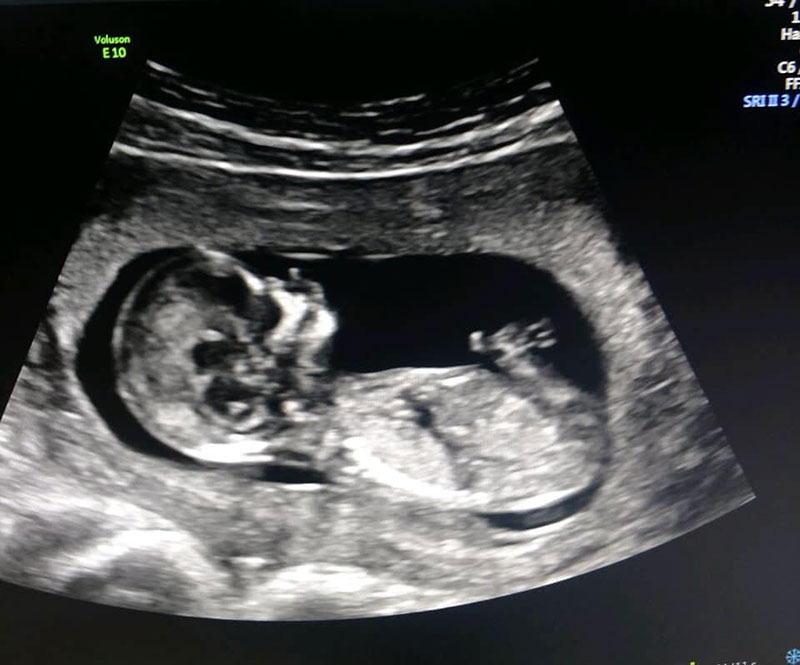

การเตรียมพร้อมที่จะมีลูกครั้งนี้ไม่ได้เกิดขึ้นแบบปุบปับ ครอบครัวทั้งสองฝ่ายต่างวางแผนเตรียมความพร้อมกันมานานร่วมสองปี โดยเมื่อถึงเวลาที่เหมาะสม พวกเขาได้ทำเด็กหลอดแก้วหรือไอวีเอฟ (IVF - In-vitro Fertilization) ซึ่งเป็นการปฏิสนธินอกร่างกาย ไข่ของเลอาถูกนำมาผสมกับน้ำเชื้อของแมทธิวเพื่อฟักเป็นตัวอ่อน และนำไปฝังในมดลูกของเซซิล สิ่งที่น่าทึ่งก็คือ ทุกอย่างผ่านพ้นไปได้ด้วยดีตั้งแต่การลองครั้งแรก เรียกได้ว่าดีเกินกว่าที่ทุกคนคาดหมาย

และแล้วในวันที่ 25 มีนาคม ที่เพิ่งผ่านพ้นมานี้เอง เซซิลก็ได้คลอดทารกเพศหญิงด้วยวิธีธรรมชาติ ไม่ได้ผ่าคลอด หนูน้อยมีน้ำหนักตัวประมาณ 2.6 กิโลกรัม อีกทั้งสุขภาพแข็งแรงดีมาก ทุกคนต่างมีความสุข แมทธิวกับเอเลียตต่างก็แฮปปี้ที่ได้เป็นคุณพ่อแล้ว เลอาเองก็ปลื้มใจที่เป็นส่วนสำคัญในการให้หลานสาวคนนี้เกิดมา